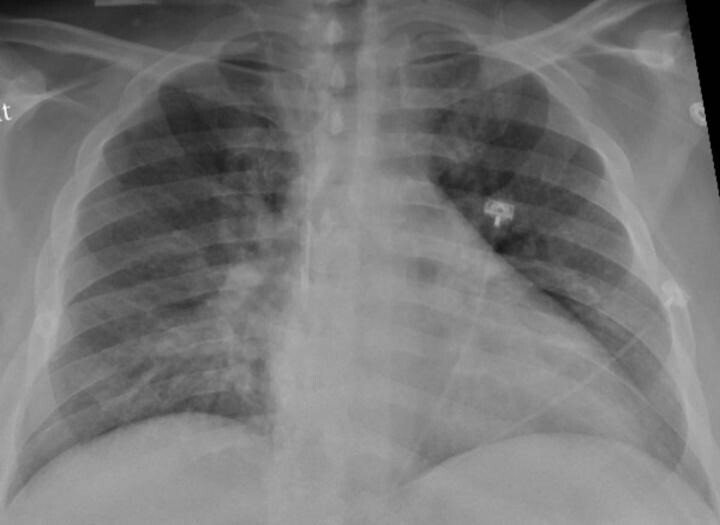

El pulmón no es un órgano estéril, sino que cuenta con su propia microbiota, formada por diferentes tipos de bacterias que influyen en la salud o en la aparición de enfermedades, concretamente un estudio ha observado que la microbiota respiratoria tiene un papel clave para evitar la aparición y empeoramiento del asma.

García Rivero, quien es además miembro de la Sociedad Española de Neumología y Cirugía Torácica (SEPAR), recuerda que en 2010 se confirmó que el pulmón sano no es un órgano estéril, sino con una microbiota pulmonar, mientras que antes se atribuía la presencia de bacterias en el tracto respiratorio inferior a enfermedades.

La microbiota respiratoria es única e influye en el estado de salud o enfermedad, al modular la inflamación a través del sistema inmune. La de la vía aérea inferior es diferente a la de la superior y los cambios en su composición se relacionan con el desarrollo de la enfermedad pulmonar obstructiva crónica (EPOC) o el asma.